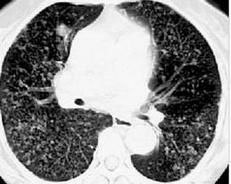

医影基础丨14 种经典肺结节影像,必须要看

肺磨玻璃结节

磨玻璃结节